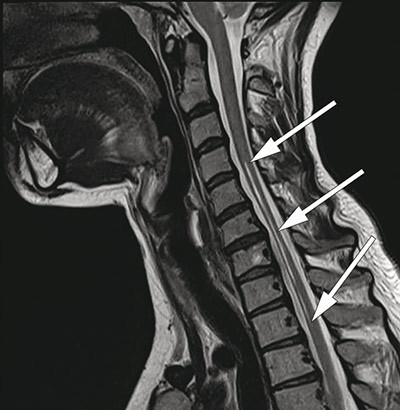

MR av ryggmargen viste markert atrofi fra nivå C4 til Th2 og to langsgående symmetriske T2-vektede høysignallesjoner fra nivå C2 til Th2 (fig 3, fig 4), lokalisert til området for anteriore horn i medulla. Forandringene ble ikke oppfattet å være forenlig med syringomyeli, demyeliniserende plakk, tumor eller transvers myelitt. Det var normale funn ved MR caput.

Det er publisert flere kasuistikker og noen få MR-studier vedrørende O’Sullivan-McLeod-syndromet, men ingen oversiktsartikler. I 1989 publiserte Gaio og medarbeidere (11) en serie med fem pasienter. MR av cervikal- og torakalcolumna ble gjennomført hos fire pasienter med T1- og T2-vektede bilder. På T1-vektet serie ble det beskrevet avflating av medulla fra C5 til Th1 og normale forhold fra C1 til C4. Funnet ble tolket som segmental spinal atrofi av medulla. Signalforandringer i medulla ble ikke påvist.

Petiot og medarbeidere (12) publiserte i 2000 en kasuistikk av en 41 år gammel kvinne med O’Sullivan-McLeod-syndromet. Pasienten hadde over en periode på 20 år utviklet en langsomt progredierende asymmetrisk svakhet i begge hender. Det var ingen nevrologiske sykdommer i slekten. MR av cervikalcolumna avdekket symmetriske høysignallesjoner på T2-vektede bilder, svarende til et område av forhorncellene som strakte seg fra nivå C6 til C7. Diameteren av cervikalmedulla ble vurdert som normal.

O’Sullivan-McLeod-syndromet er en sjelden form for distal spinal muskelatrofi med forholdsvis god prognose. Diagnosen bygger på kliniske og nevrofysiologiske undersøkelser og karakteristiske MR-forandringer med segmental atrofi i cervikalmedulla og høysignallesjoner i området svarende til fremre motornevron.